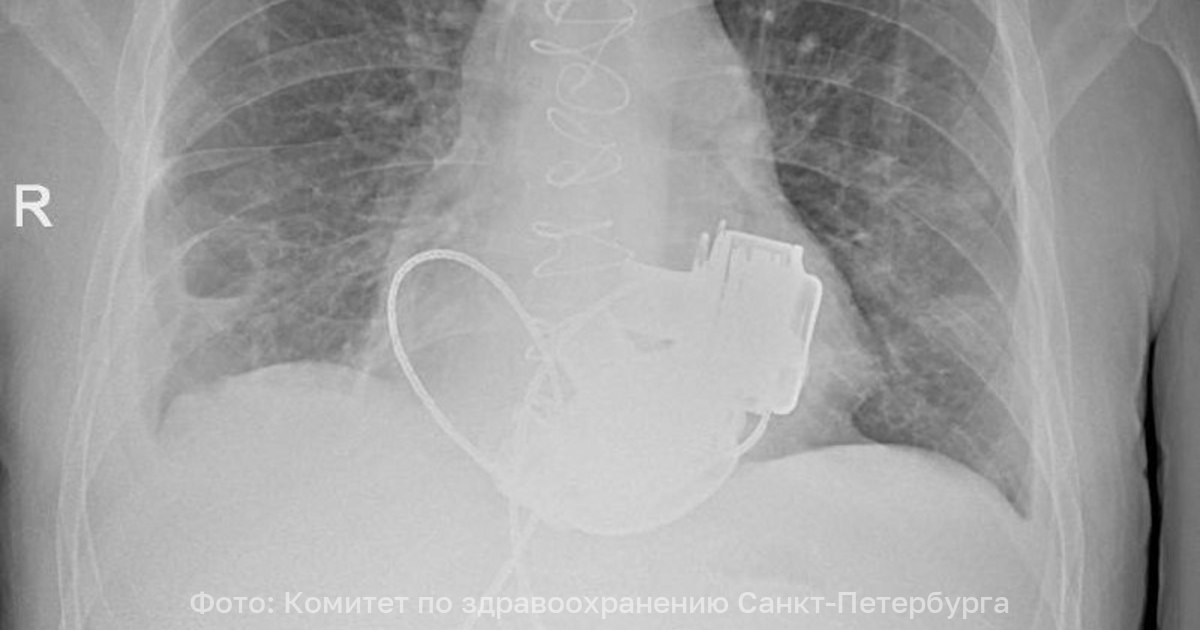

В Санкт-Петербурге врачи готовят к выписке пациента, который теперь живёт без пульса. В конце ноября 2025 года 36-летнему мужчине имплантировали одновременно левый и правый искусственные желудочки сердца. Об этом рассказали в городском комитете по здравоохранению.

«Операция продолжалась около 4 часов. Для наших специалистов самым сложным было синхронизировать работу двух искусственных желудочков сердца, но с этой задачей мы успешно справились. Это доказывает высокий уровень развития кардиохирургии в нашем городе». — отметил главный внештатный специалист по сердечно-сосудистой хирургии Санкт-Петербурга Геннадий Хубулава.